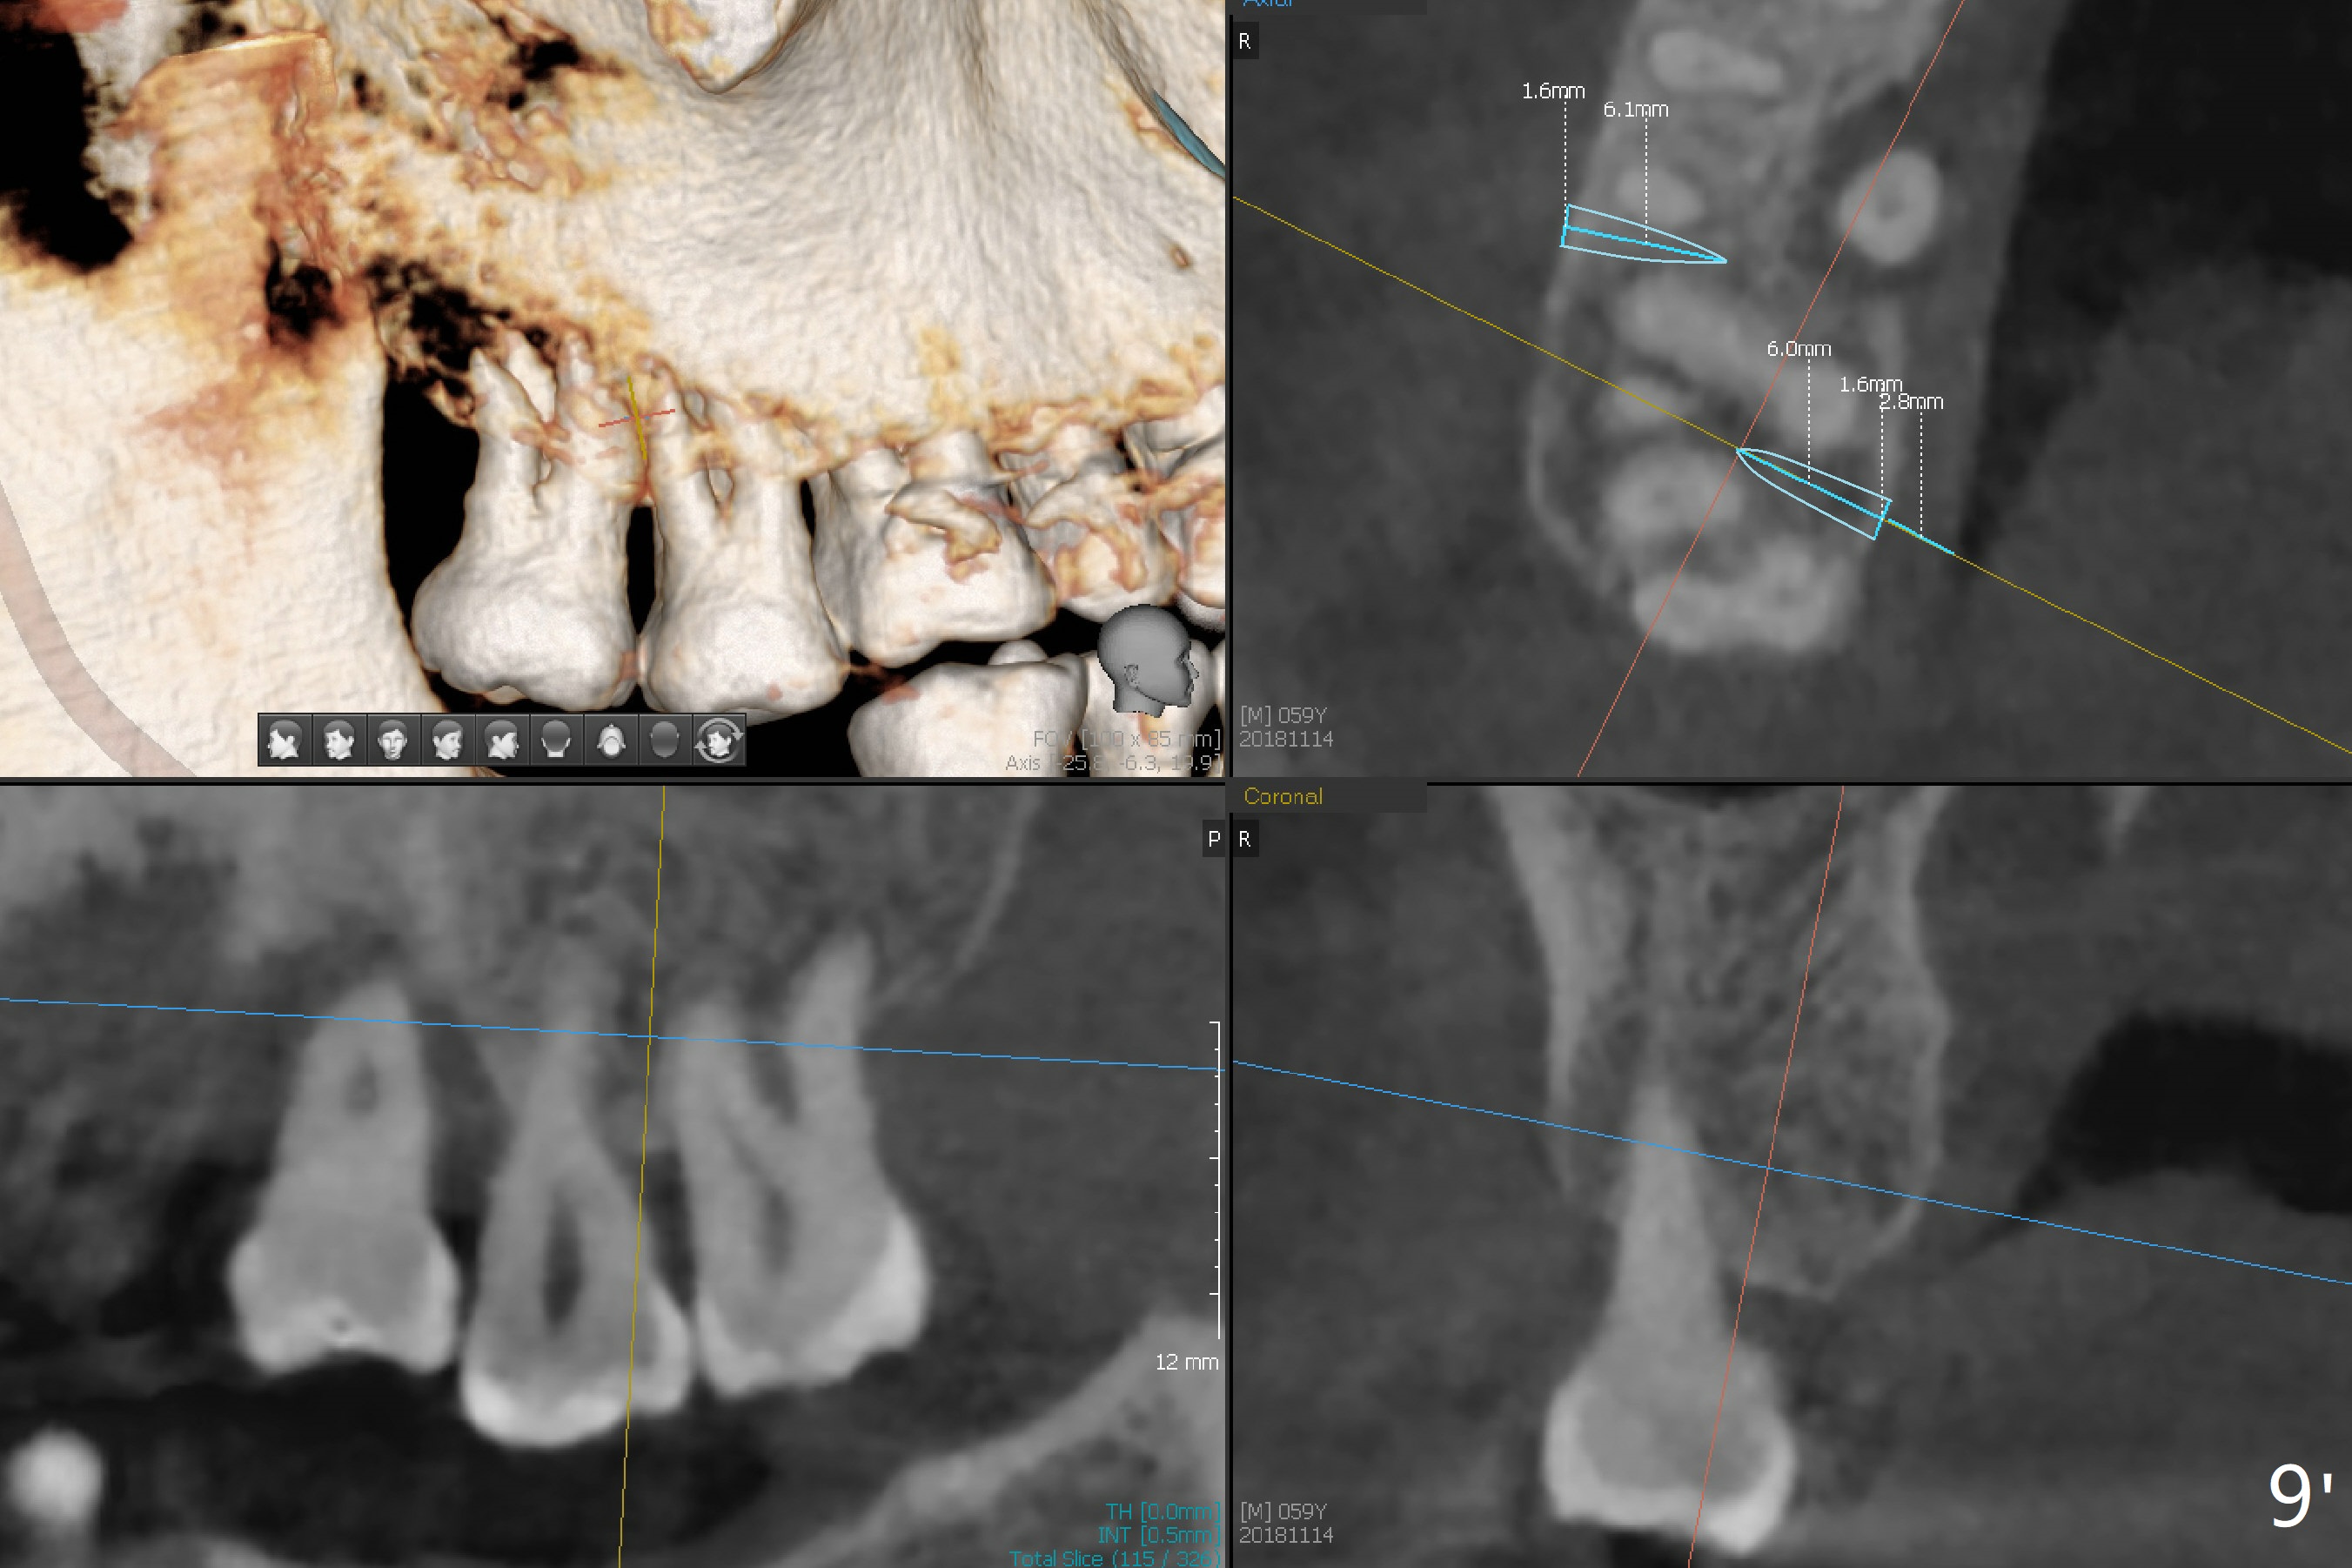

CBCT axial section shows that there is not enough space for mini implant placement at the tooth #2 (Fig.9', coronal to the apices (axial section)).